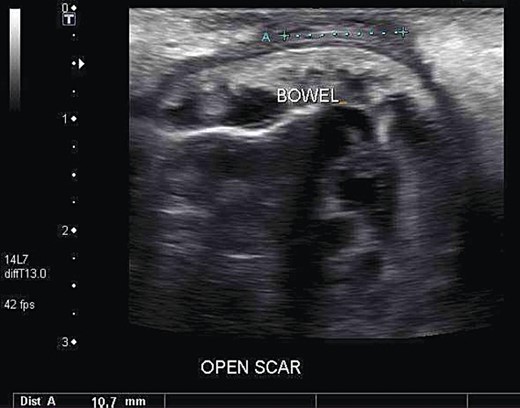

On Day 4 postpartum, wound dehiscence was noted. There were no clinical signs of infection, wound swab cultures grew normal skin flora only and blood tests (including inflammatory markers) were normal. On Day 5 postpartum however, she experienced nausea and vomiting. An ultrasound of her abdomen and pelvis was therefore ordered. This revealed a large defect on the anterior abdominal wall with small bowel herniation adjacent to the skin (see Fig. 1).

Ultrasound of the patient's abdominal wall, revealing a large defect with small bowel herniation adjacent to the skin.